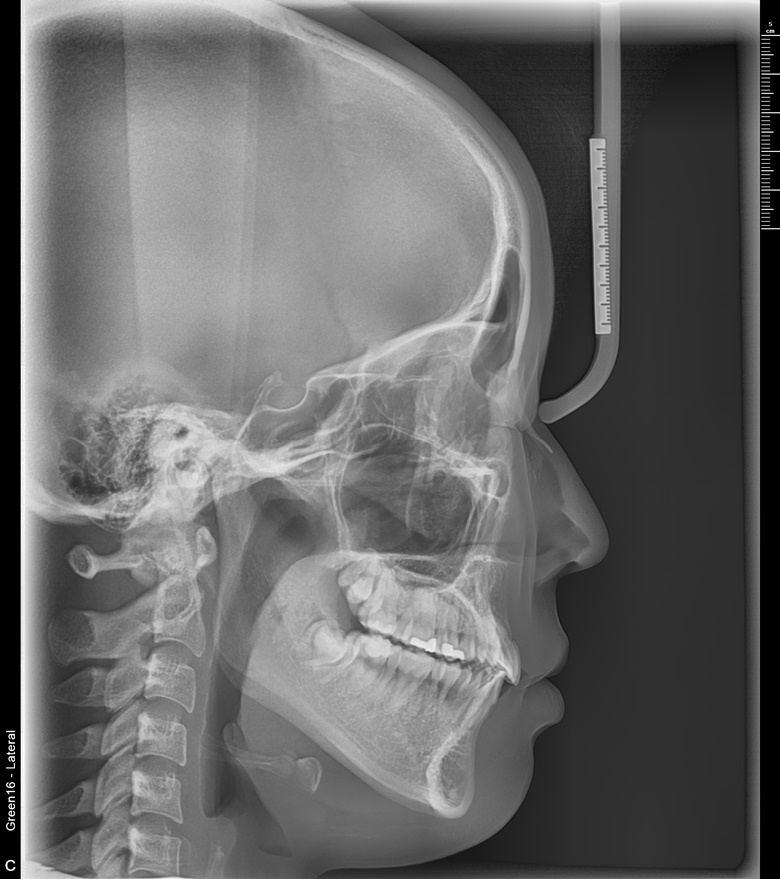

치료 전 사진입니다.